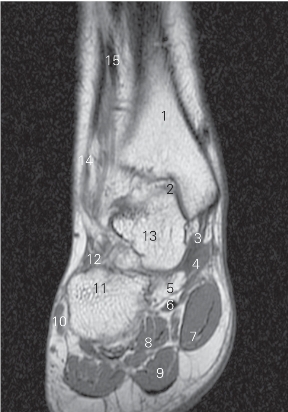

图5-59 经内踝管的足冠状断层MR T1加权图像

1 胫骨 tibia 2

长屈肌 flexor hallucis longus

3 趾长屈肌 flexor digitorum longus 4 跟骨 calcaneal

5 趾短屈肌 flexor digitorum brevis 6 第一跖骨 1st metatarsal bone

7 足底肌 sole muscle 8 胫骨后肌 tibialis posterior

图5-60 经第一跖骨的足冠状断层MR T1加权图像

3 距骨 talus 4 跟骨 calcaneus

5

长屈肌腱 tendon of flexor hallucis longus

6 足底方肌 quadratus plantae 7 小趾展肌 abductor digiti minimi

8 趾短屈肌 flexor digitorum brevis 9 足底肌 sole muscle

10 第一跖骨 1st metatarsal bone 11 内侧楔骨 medial cuneiform bone

12 舟骨 navicular bone

图5-61 经内侧楔骨的足冠状断层MR T1加权图像

1 胫骨 tibia 2 距骨 talus

3 胫骨前肌 tibialis anterior 4 舟骨 navicular bone

5 跟骨 calcaneal 6 骰骨 cuboid bone

7 腓骨长肌 peroneus longus 8 小趾展肌 abductor digiti minimi

9

趾 great toe 10 足底肌 sole muscle

11 第一跖骨 1st metatarsal bone

12

长伸肌腱tendon of extensor hallucis longus

13 内侧楔骨 medial cuneiform bone